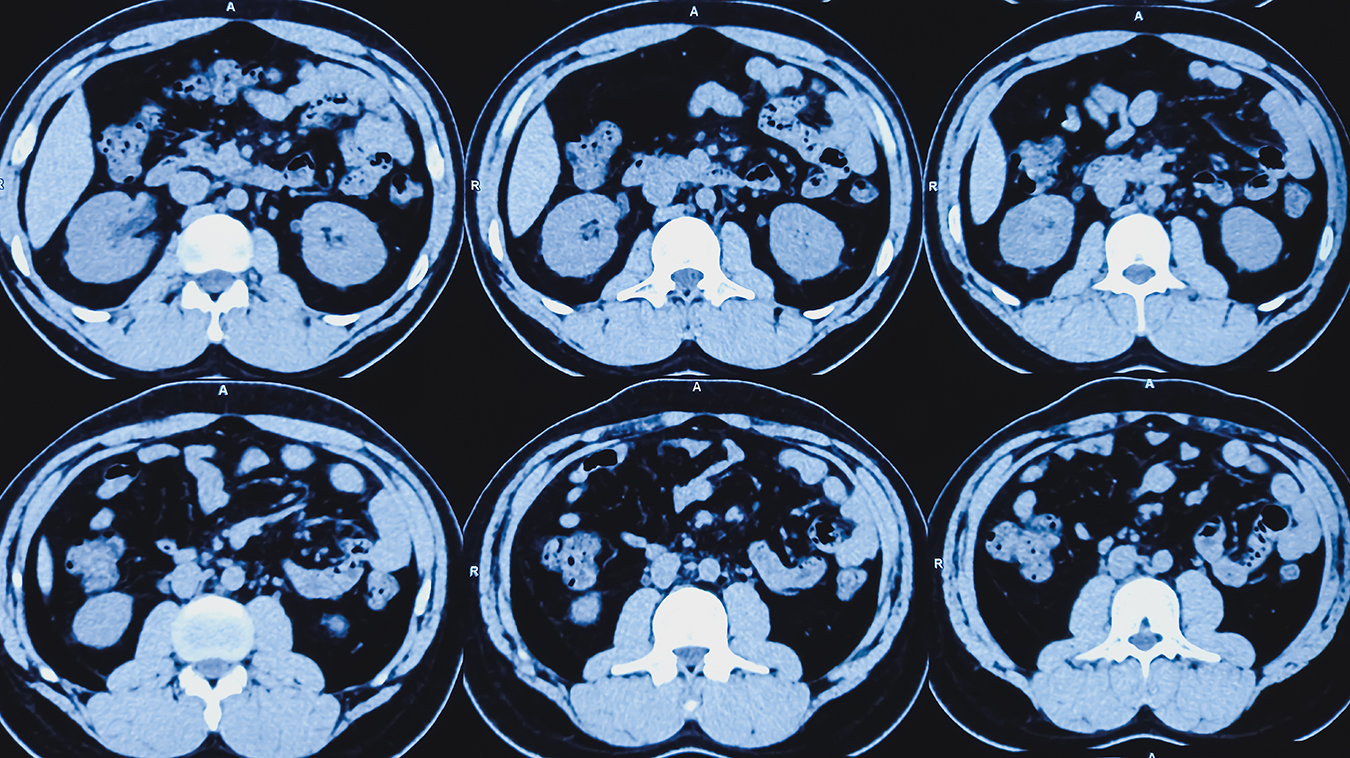

During a CT scan, a rotating X-ray source emits a narrow beam of photons through the body part of interest which is then recorded by an advanced detector on the other side. This results in a volumetric dataset that the computer reconstructs into numerous cross-sectional images, called tomographic images or slices. This creates three-dimensional (3D) images that can be viewed from multiple directions.

CT scans are very good at imaging bone but can also provide detailed information about soft tissues in the chest, abdomen, and pelvis, in addition to blood vessels. A CT may be preferred to evaluate fractures or look for cancers or blood clots.